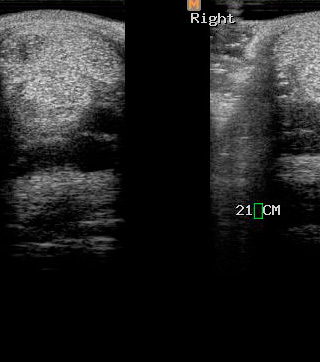

Ecografía

Cuenta con Ecografía digital de alta complejidad.

17 años de experiencia siendo una de las ecografistas más reconocidas en la práctica de equinos. Realiza pasantías en la universidad de Davis California y en Mid-Atlantic Equine Medical Center en New Jersey.